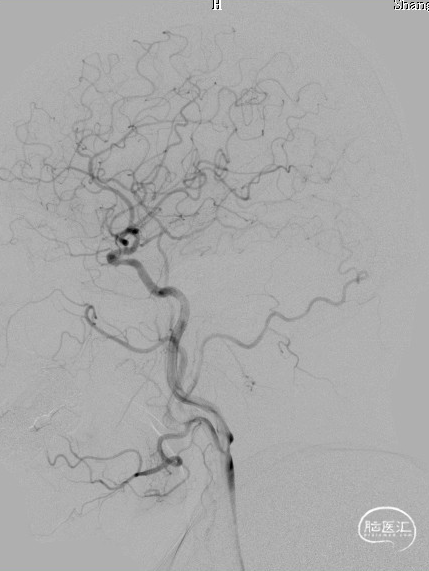

DSA:LSub。

DSA:L-CCA。

0.018*300cm 外周导丝至左肱动脉,0.014*200cm 通桥北斗SS™神经血管导丝超选至左椎V2段远端。

沿0.018*300cm 外周导丝送入6*40 外周球囊送至左侧锁骨下动脉狭窄处,压力泵逐渐加压到6atm。

撤出球囊后见残余狭窄40%。

再次沿0.018*300cm 外周导丝送入6*40 外周球囊达LSub狭窄部位,压力泵逐渐加压到8atm,见残余狭窄20%。

造影见LV闭塞,立即沿0.014*200cm 通桥北斗SS™神经血管导丝置入3mm*16mm 药物球扩支架至LV1。

压力泵逐渐加压球扩支架到8atm, 支架打开良好,造影示残余狭窄0%。

双侧锁骨下动脉造影见椎动脉、基底动脉血流通畅,远端未见栓塞表现。